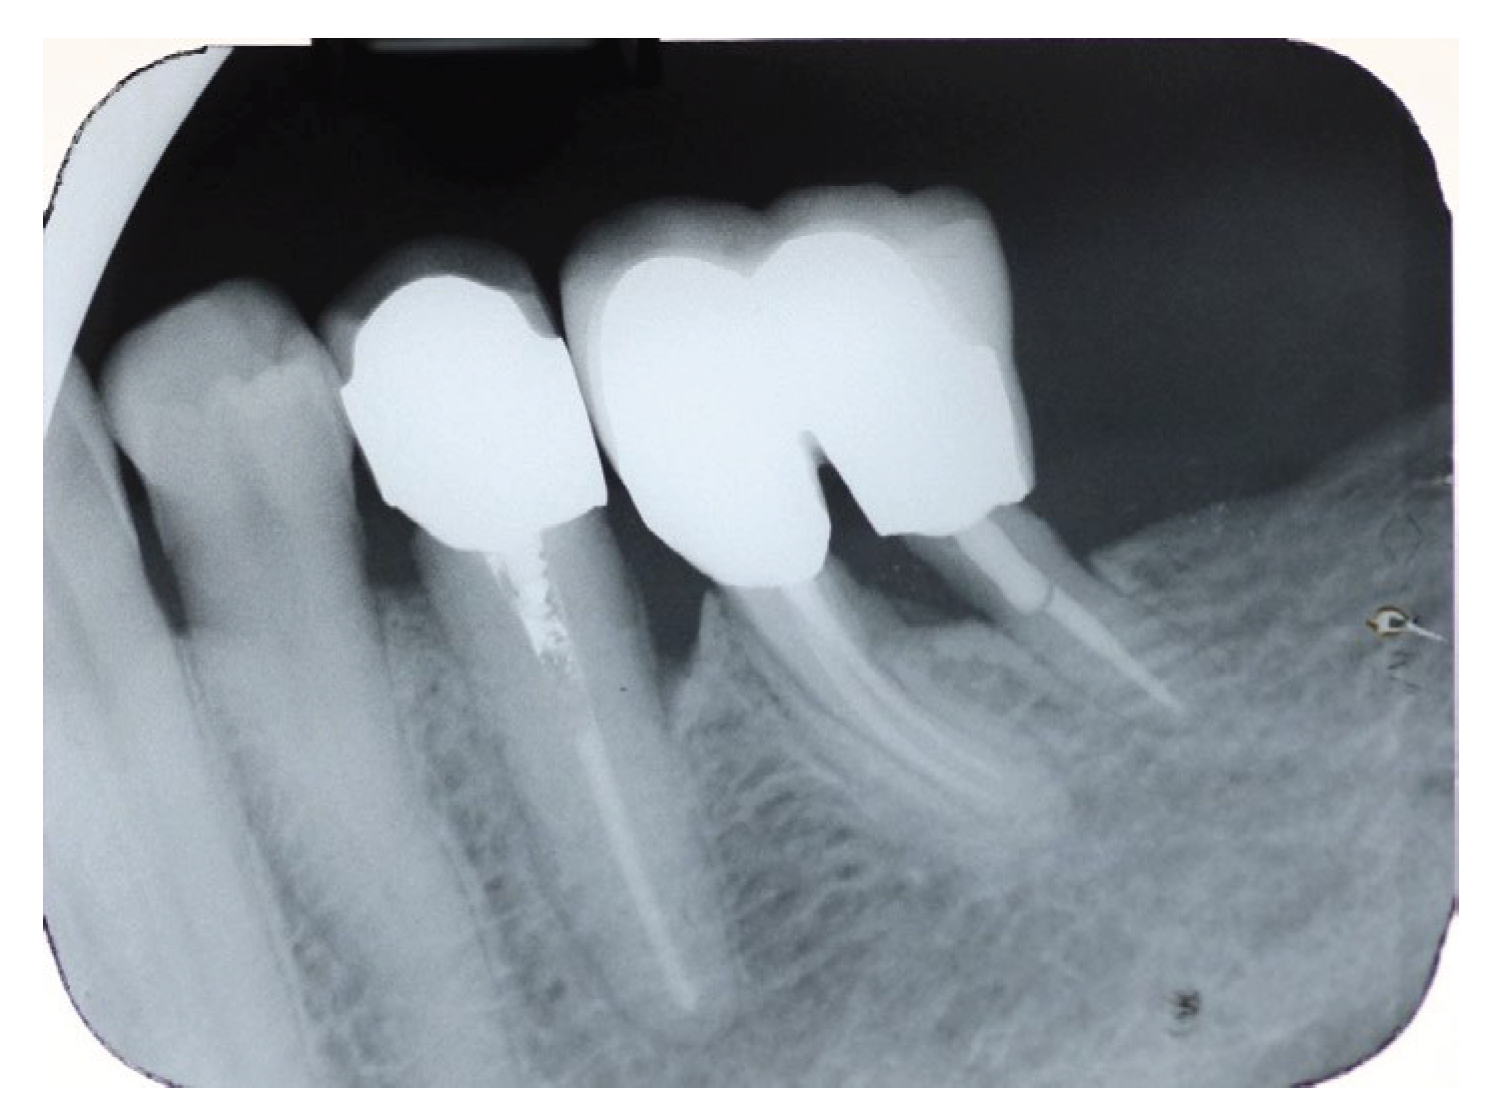

A periapical radiograph in the molar region of #46-47 teeth revealed that there was a radiolucent area in the middle third of the mesial root of tooth #47. This lesion was located mesially and it seems to be rather well defined in this area but coronally the bone loss had a J-shape appearance. In addition, subgingival carries in the distal roots of #47 and #46 were also detected (Figure 2). Both teeth had been restored with cast posts and splinted fused to metal ceramic crowns. Crestal bone between the two teeth appeared to be moderately resorbed.

Figure 2. Periapical X-Ray of #46, #47.